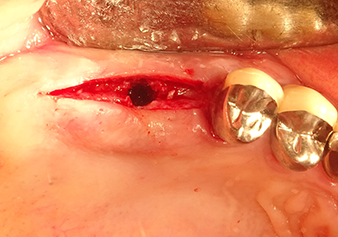

Подготовка ложа имплантата и наращивание

После промежуточного контроля (рис. 4) был проведен еще один этап подготовки (рис. 5). За тем, с помощью гидравлического инструмента Z35P мембрана была поднята в нужное положение (рис. 6 и 7). Далее, следовала дальнейшая пьезохирургическая подготовка ложа для имплантата, завершенная с помощью ротационного бора и лопаточной фрезы до диаметра имплантата 4,8 мм. Перед установкой имплантата под мембрану Шнейдера был введен аугментационный материал (размер частиц около 0,8-1,6 мм) (рис. 8).